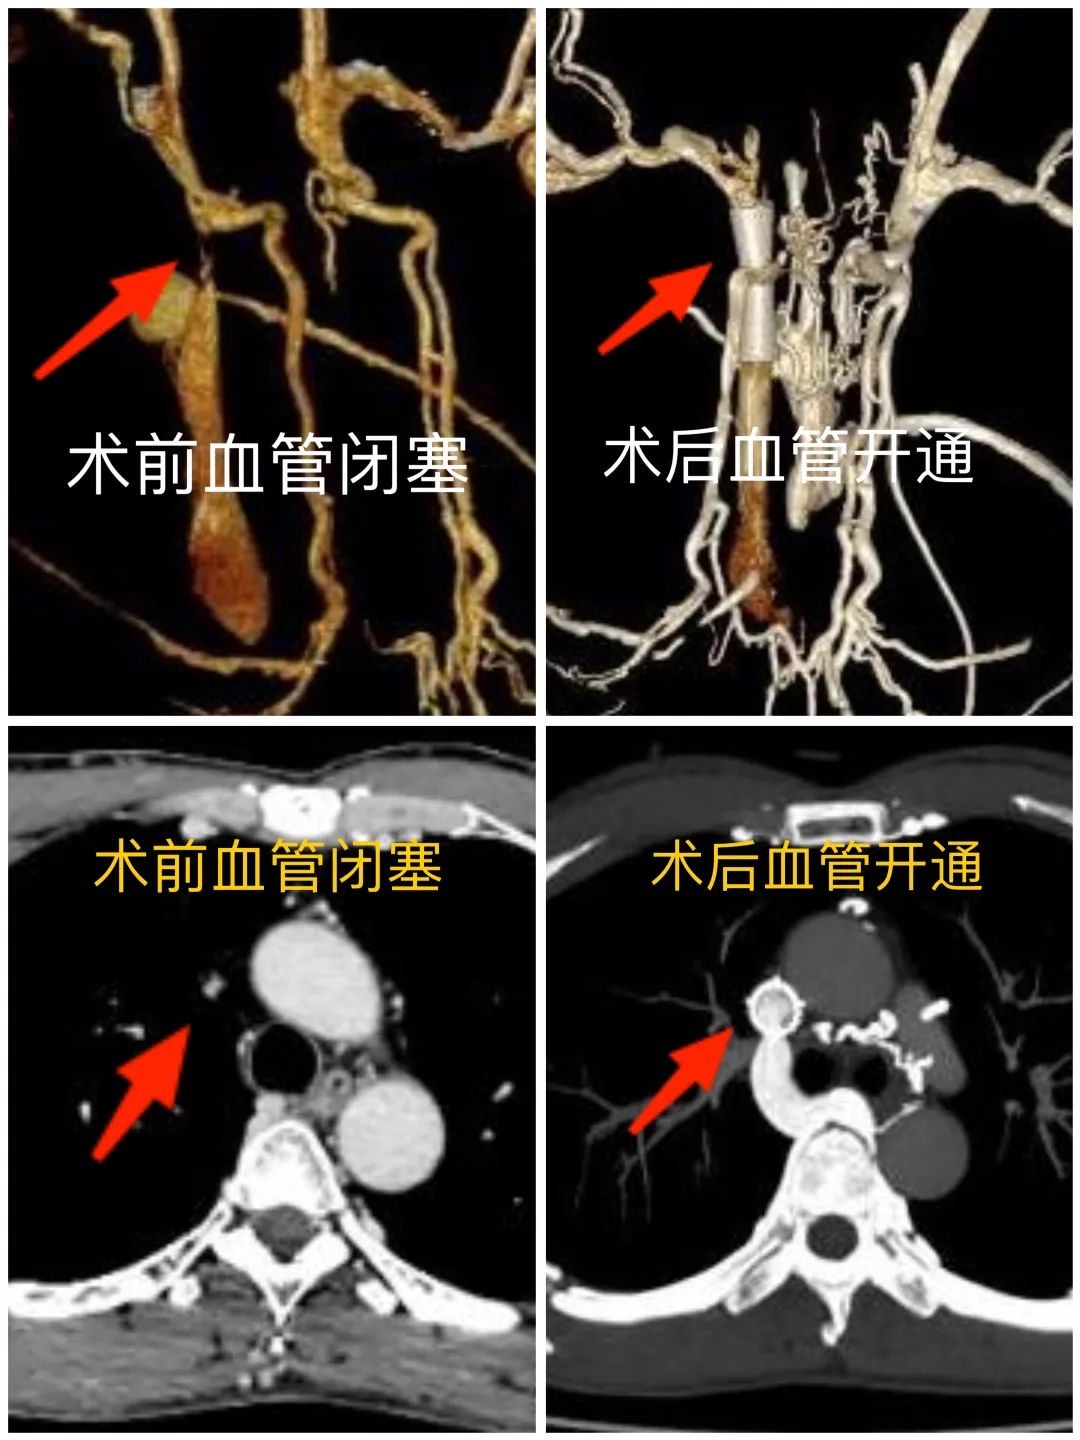

上腔静脉上段闭塞,伴奇静脉、胸廓内静脉、胸壁静脉曲张,左侧头臂静脉汇入异常,伴纵膈静脉侧支血管形成......

在于主任的指导下,侯军、姜海军副主任医师为老张做了【上腔静脉支架球囊扩张+支架植入术】。

术中,通过造影可见,老张的血管迂曲严重,走向分支错综复杂,导丝找到“堵点”后反复尝试探行,毫厘之间小心翼翼地变化角度位置,寻找“突破点”,终于扩开了约3厘米长的闭塞段,并成功植入支架,顺利地为血流钻出一条畅行通道。

老张各种不适症状明显缓解